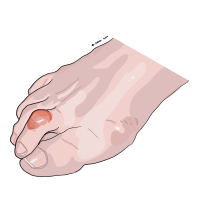

Hallux valgus

Hallux valgus innebär i princip att stortån är sned och pekar mot de andra tårna.

Ibland trycks stortåleden ut och ger upphov till en svullen, inflammerad knöl på insidan foten.

Hallux valgus anses dels bero på ärftliga betingelser och dels på miljön med smala skor och hyperpronation som exempel.

Den kirurgiska behandlingen utgörs förenklat av att man sågar bort knölen på insidan foten, samt att man sågar av ett av stortåledens ben varpå man kan korrigera den snedställda stortåns riktning och återigen få en rak tå.